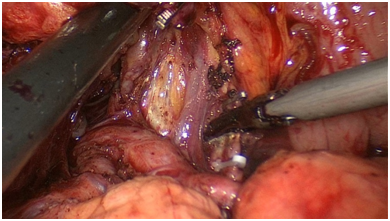

手术图片

腹腔镜直肠癌根治术

腹腔镜胃癌根治术

腹腔镜结肠癌根治术。